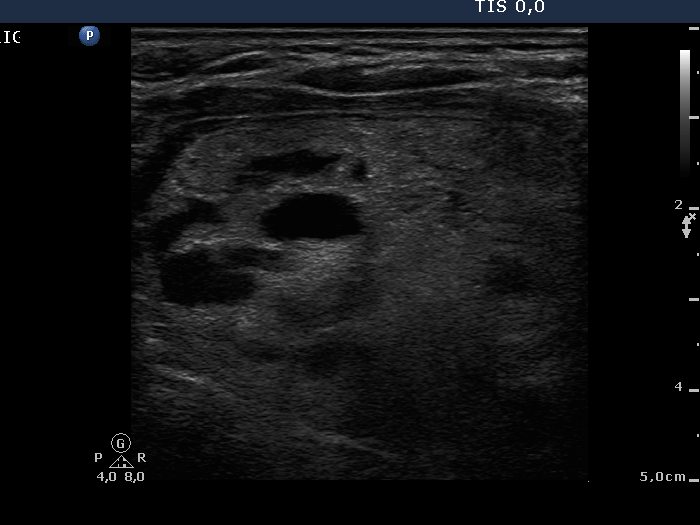

Benign Hashimoto's thyroiditis (cytological diagnosis) - case 1251

First, we demonstrate two cases of Hashimoto's thyroiditis with pronounced fibrotic changes. Both present pale and bright hyperechogenic granules and lines corresponding to normal and excessive connective tissue. Neither of the discrete areas are nodules in a pathological sense.